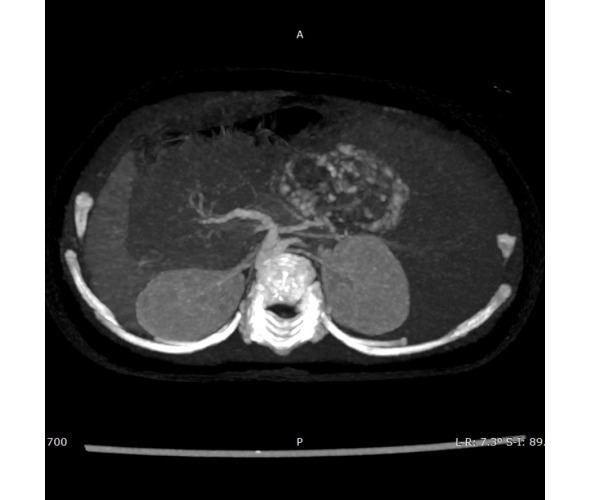

Fig. 21 Focal hemangioma of the liver. CT data with contrast. MIP reconstruction of the image.

Focal hemangioma of the liver (28%) is a rapidly involuting hemangioma that regresses immediately after birth. The incidence in boys and girls is the same. About 15% of children have infantile hemangiomas on their skin. More than 90% of the tumor volume decreases by 1.5—2 years of age.